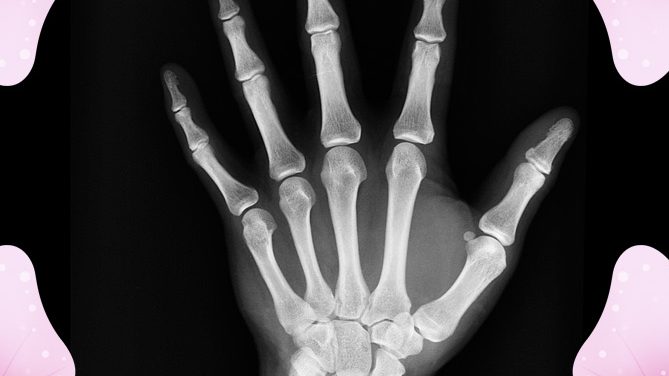

Bone loss and bone weakening is a major concern for many women especially when getting older. The diagnoses of osteopenia and osteoporosis are dreaded ones not alone because it makes many of us feeling helpless.

A year ago, Jackie Prete had been diagnosed with osteoporosis (bone loss) after a bike accident. This was on the heels of dealing with osteopenia (reduced bone mass) for a number of years prior to that. The numbers were very high and the doctors pressured her intently to take drugs. She refused.